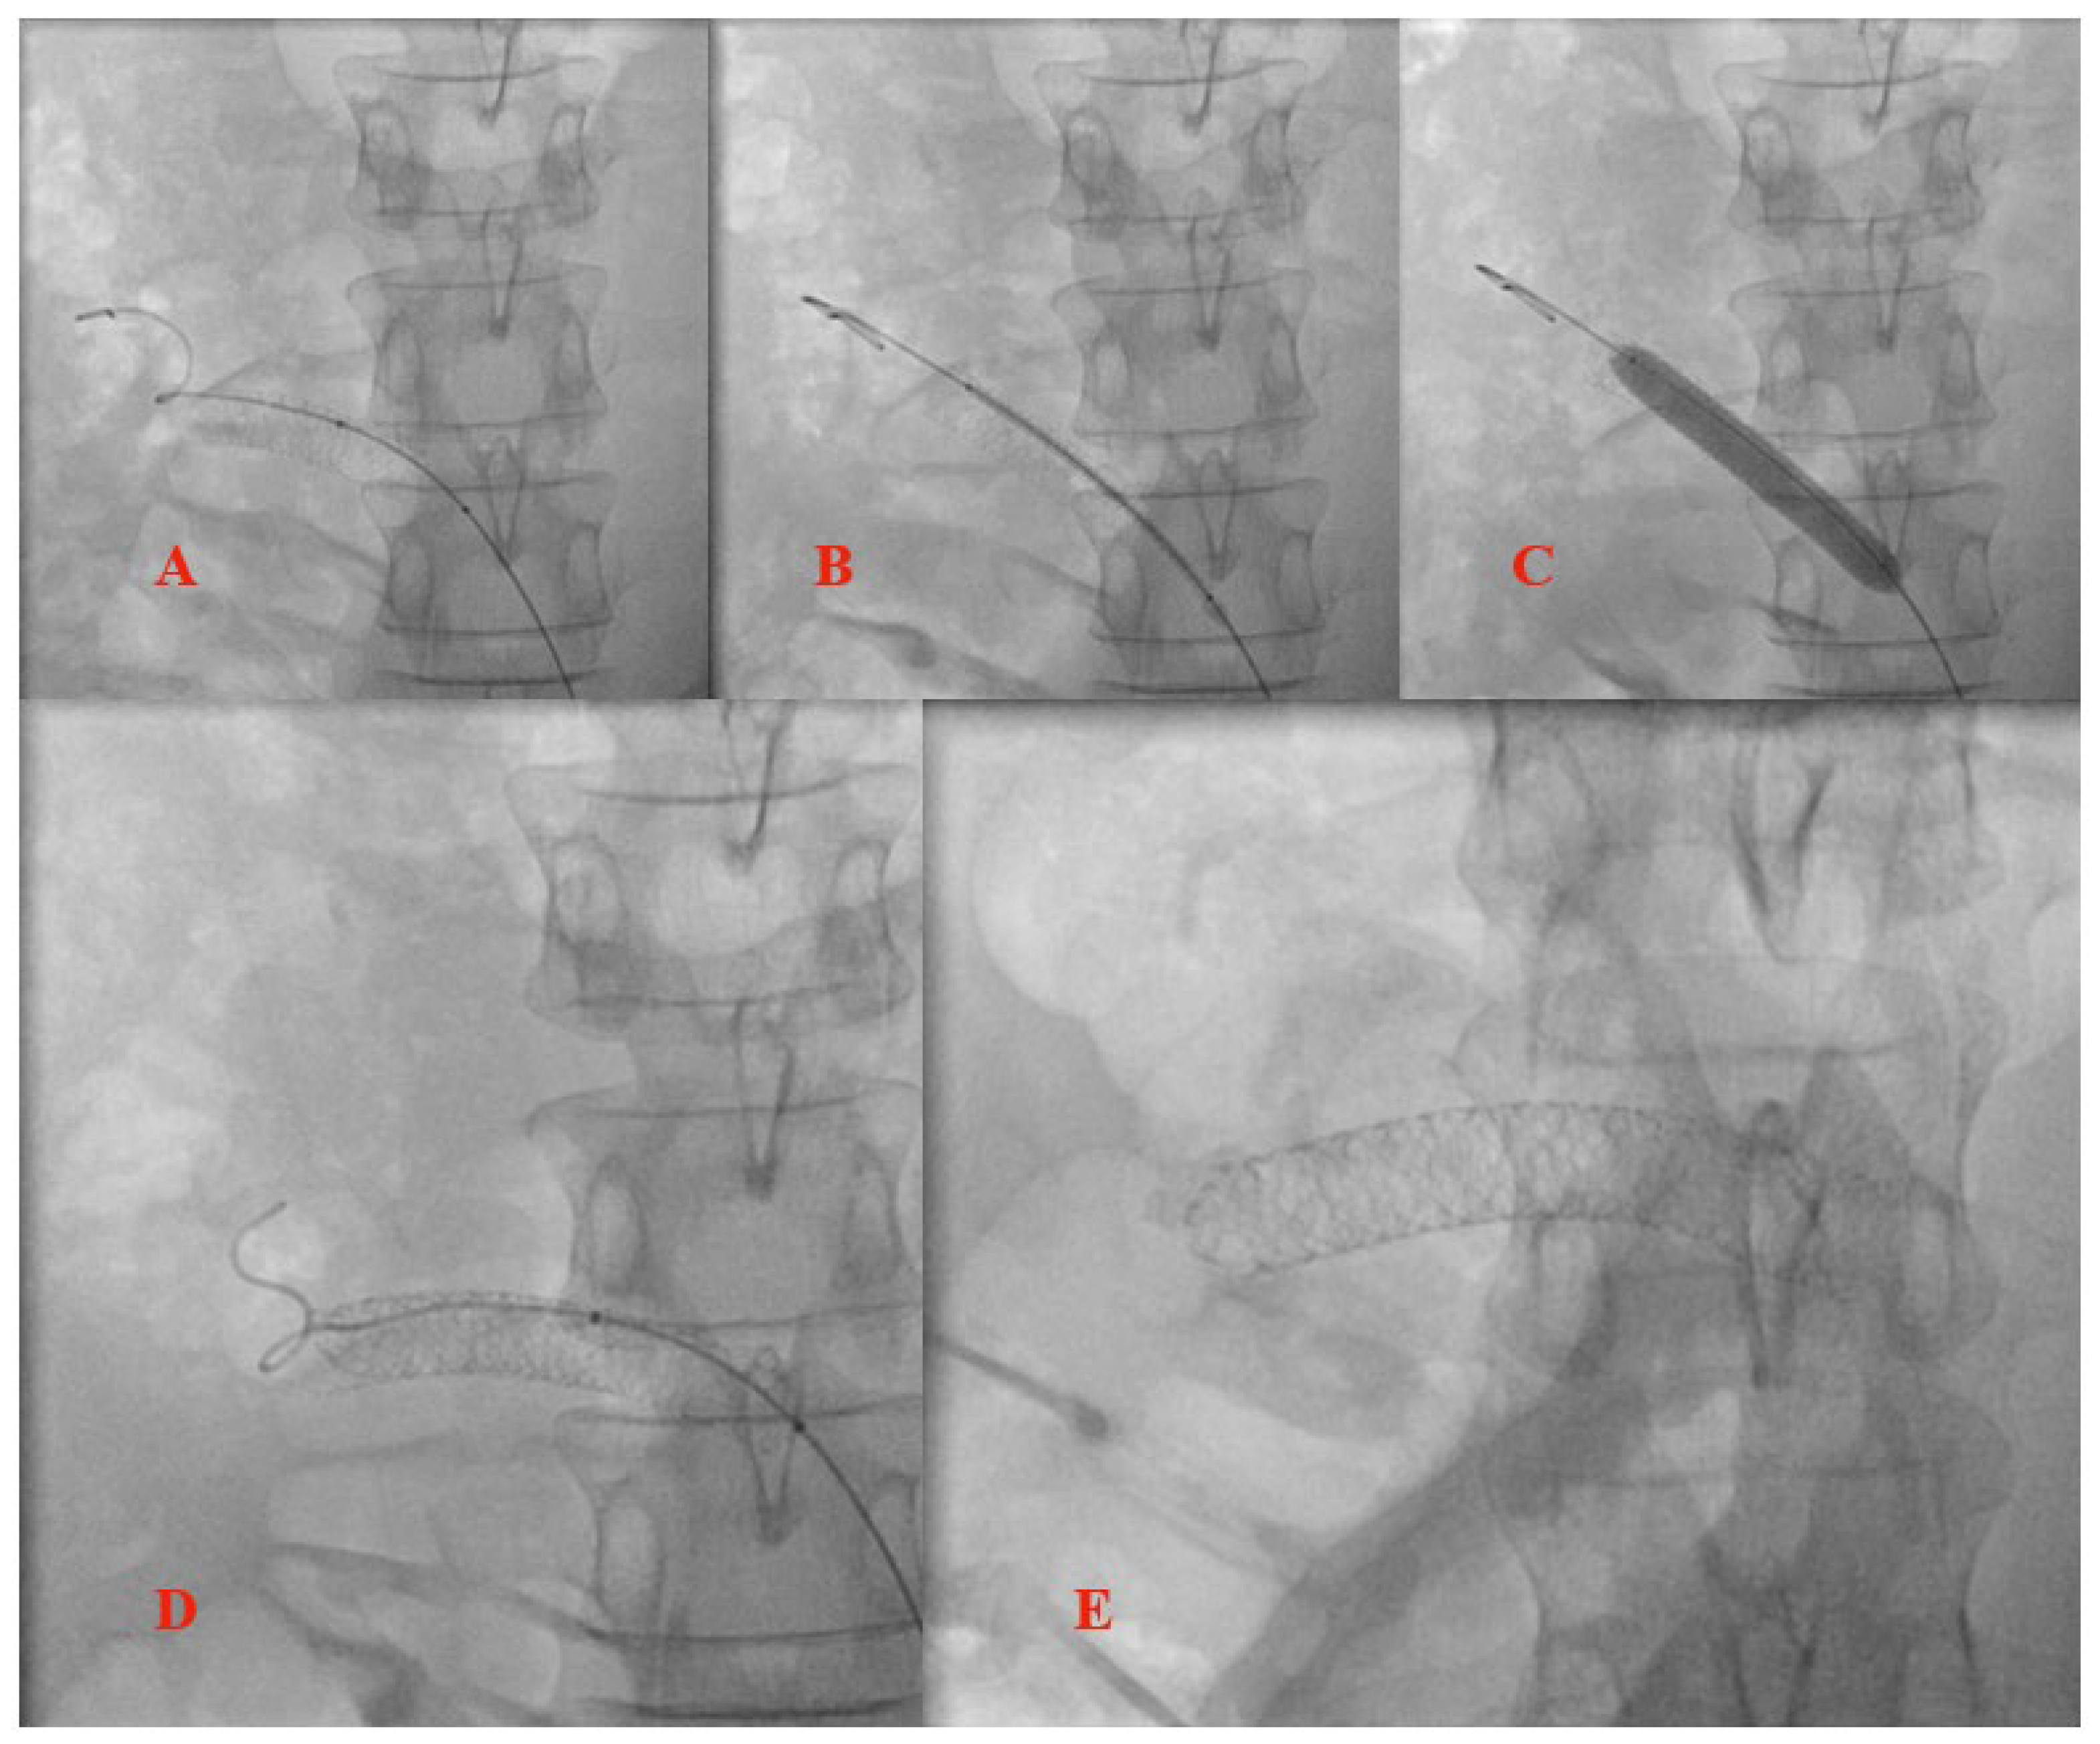

3.1. Case Report

4. Surgical or Interventional Management